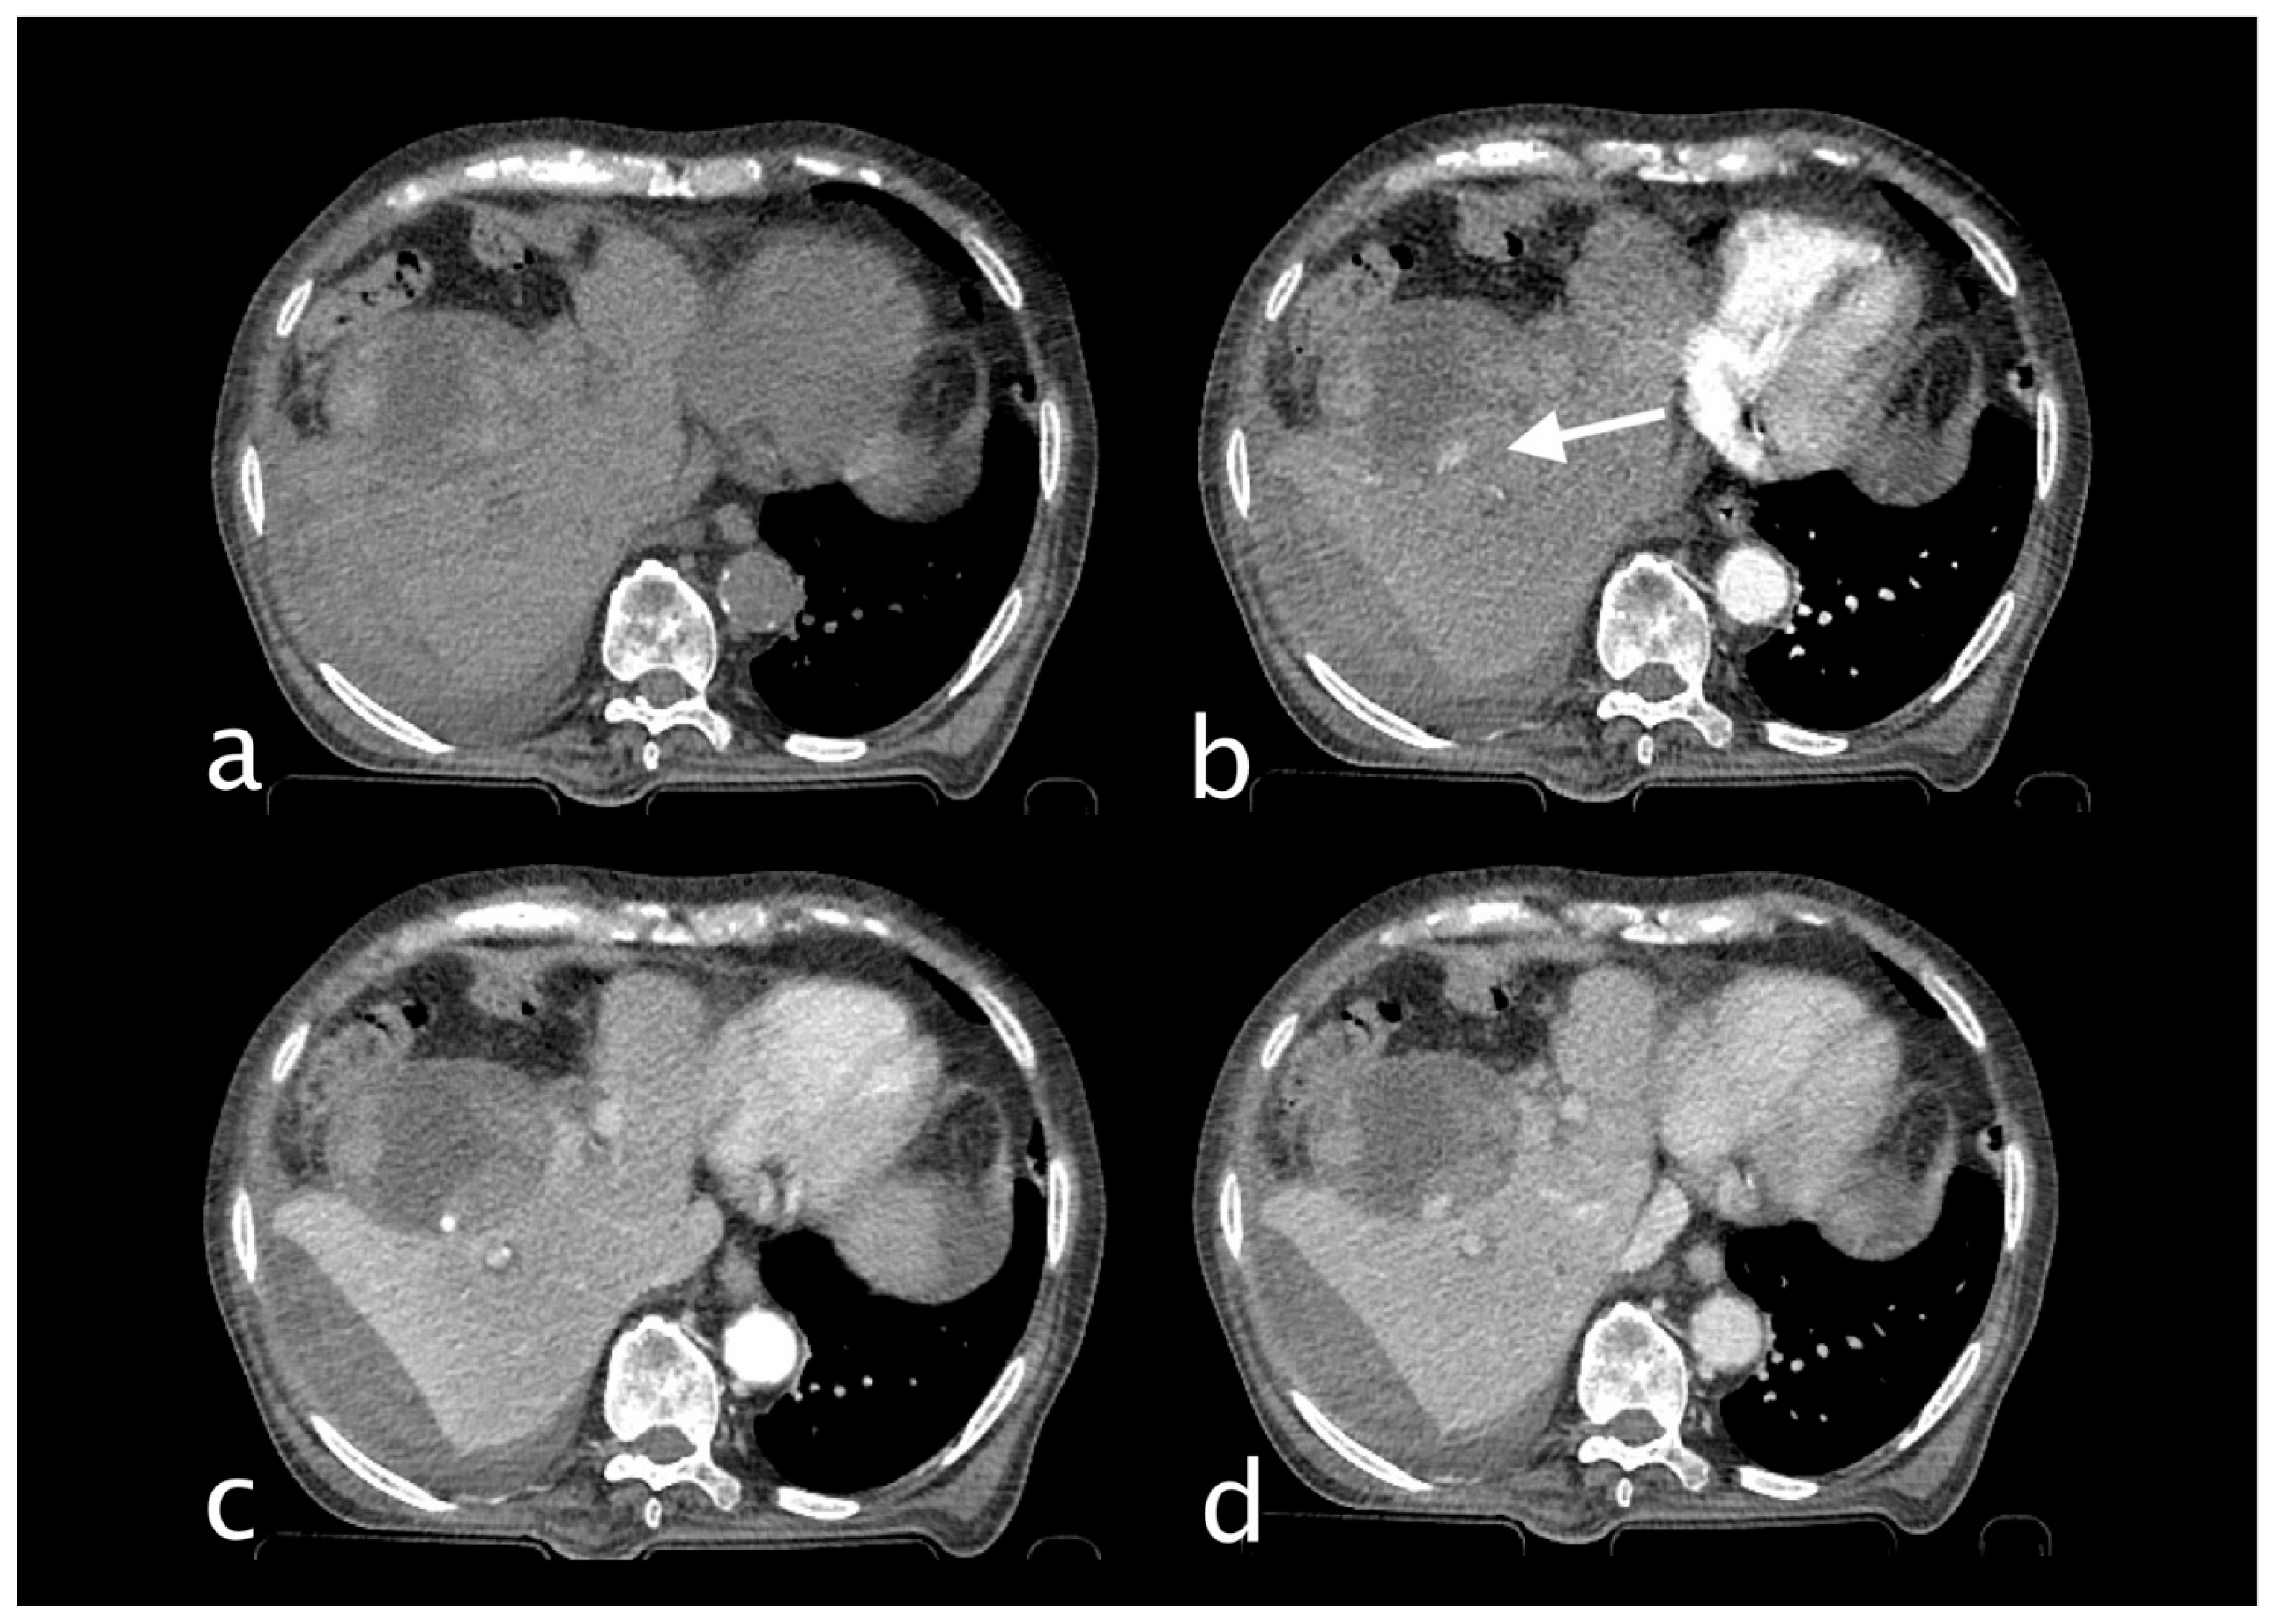

2. Imaging